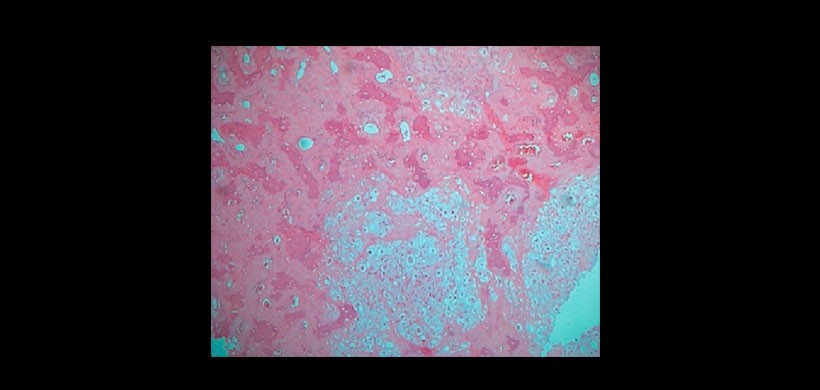

Figura 4: La vista de baja potencia de la lesión muestra tejido condroide con áreas de diferenciación ósea en forma de trabéculas óseas. (Mancha H & E, × 40).